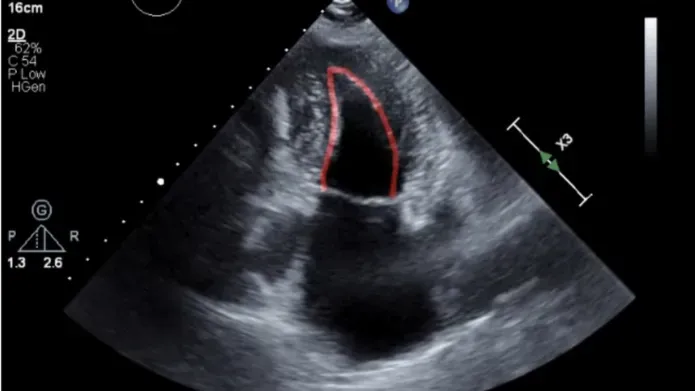

Experts at the University’s School of Medicine utilised AI to scan images of the heart to identify patients with heart failure from population based electronic health records and echocardiography heart scans. The project was carried out utilising state-of-the-art technology from software developer Us2.ai and was funded by Roche Diagnostics International. The full findings have been published in the journal ESC Heart Failure.

“Echocardiography heart scans that were enhanced by the AI software helped to provide more measurements - or parameters - of heart structure and function that can be used to help diagnose heart failure. These measurements were not routinely reported by the usual heart scans from the electronic health records.

“When compared to reports generated by routine heart scans, those enhanced by AI were more detailed and could also be processed at a larger scale than conventional images.